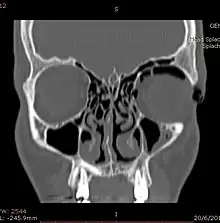

Woman with preorbital swelling in orbital emphysema shown in CT scans | |

Computed tomography (CT)

Computed tomography is effective and sensitive in the diagnosis of orbital emphysema,[3][37] as it can confirm the anatomical location and size of air, bony defects, indentation of the eyeball, and the condition of the optic nerve, as well as the presence of any extraocular muscle entrapment and herniation of preorbital fat into the sinus cavities.[3][15][38] The location of the orbital emphysema is present near the site of the fracture.[1][3] The scans are usually taken along the transverse plane. Transverse images allow the evaluation of fractures in medial and lateral orbital walls. By reformatting these transverse images or taking coronal images, the examination of orbital floor and roof is permitted. Helical scanning is preferred as it has a lower imaging time and radiation dose comparing to conventional scanning, especially when reforming transverse helical scans into coronal images.[3] The staging of orbital emphysema can then be determined with visual acuity examination and ophthalmoscopy.[6] A disadvantage of using a CT scan is that when detecting air after orbital trauma, the presence of a wooden foreign object can give a false positive result of orbital emphysema. The wooden object can mimic the presence of orbital emphysema. Therefore, patients’ medical history is crucial in making the correct diagnosis.[3]